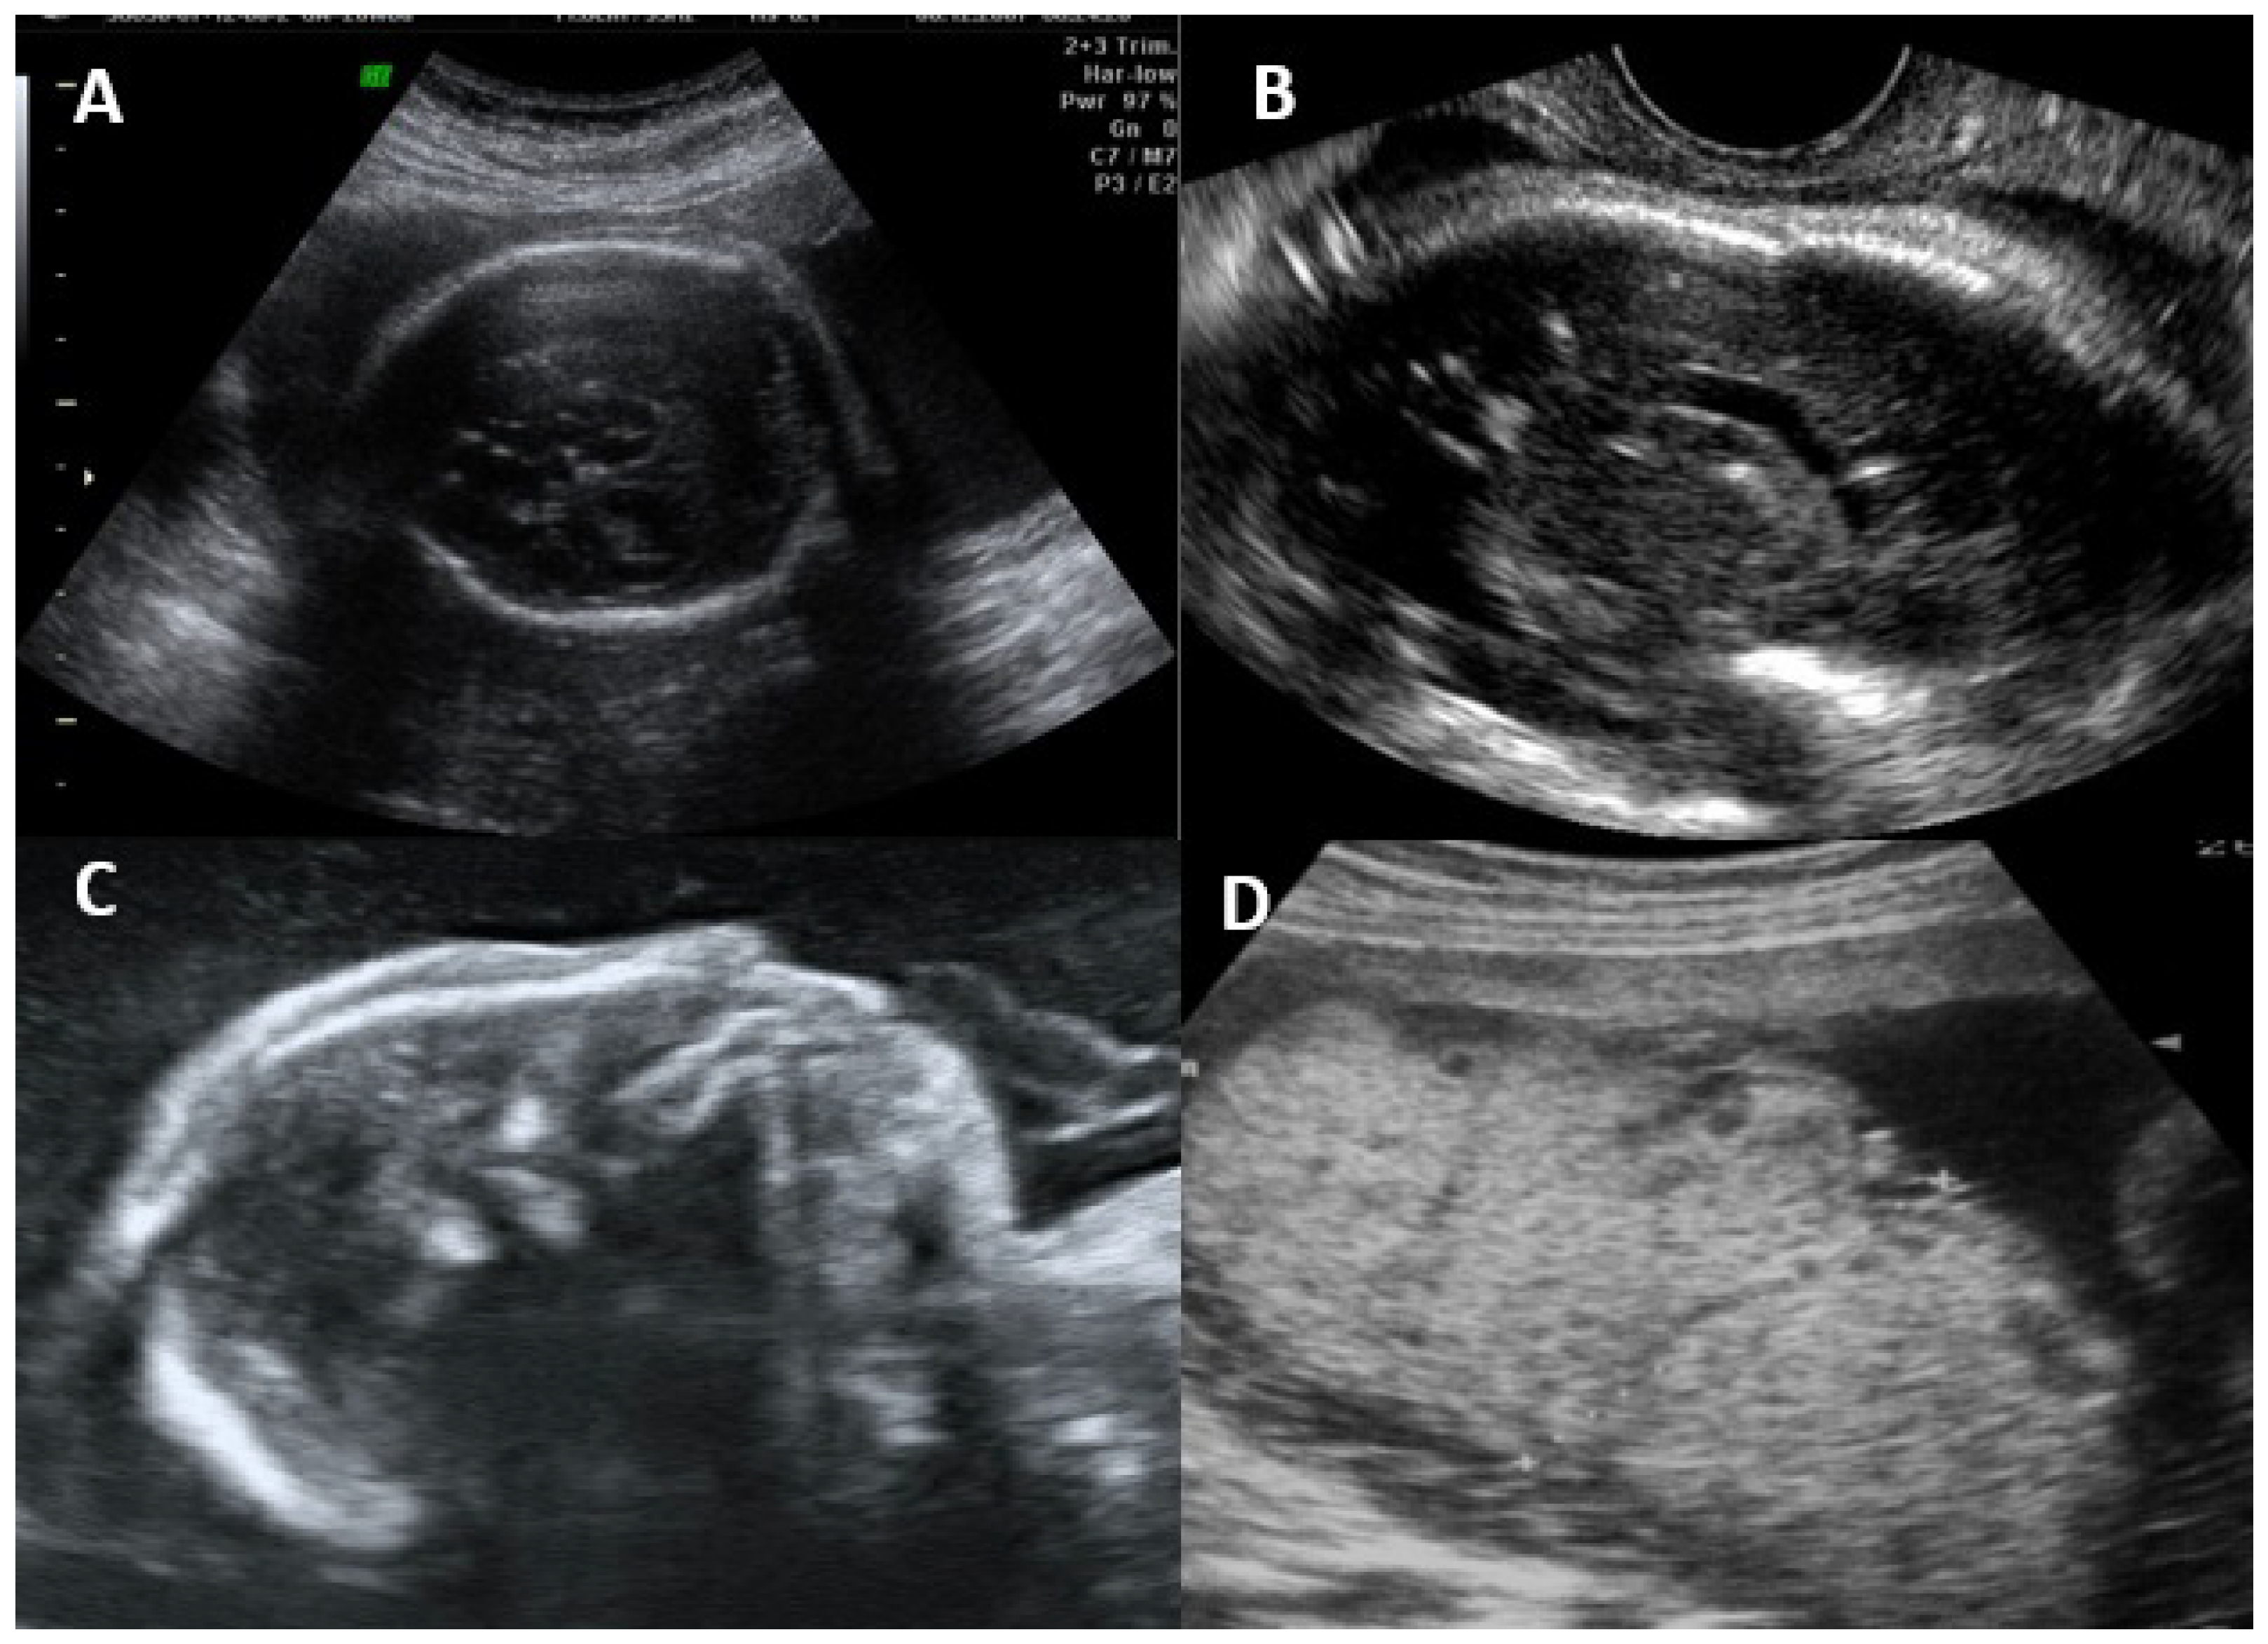

Ultrasonographic and Magnetic Resonance Imaging Findings

- Rybak-Krzyszkowska, M.; Górecka, J.; Huras, H.; Staśkiewicz, M.; Kondracka, A.; Staniczek, J.; Górczewski, W.; Borowski, D.; Grzesiak, M.; Krzeszowski, W.; et al. Ultrasonographic Signs of Cytomegalovirus Infection in the Fetus- A Systematic Review of the Literature. Diagnostics 2023, 13, 2397. [Google Scholar] [CrossRef]

| Extra-CNS | |

| FGR Abnormal amniotic fluid volume Ascites and/or pleural effusion Skin edema Hydrops Placentomegaly >40 mm Hyperechogenic intestines Hepatomegaly >40 mm (right lobe) Splenomegaly >40 mm (largest diameter in the second trimester) Hepatic calcifications Cardiomegaly |

|

| CNS | |

| Moderate ventriculomegaly <15 mm Isolated cerebral calcification Isolated interventricular adhesion Vasculopathy/hyperechogenicity of lenticulostriate vessels |

| Severe CNS malformations | |

| Ventriculomegaly >15 mm Periventricular hyperechogenicity Hydrocephalus Microcephaly <3 SD Mega cisterna magna >10 mm Hypoplasia of vernix or cerebellum Porencephaly Lissencephaly Periventricular cysts Corpus callosum abnormality |

| Ultrasound or MRI | |